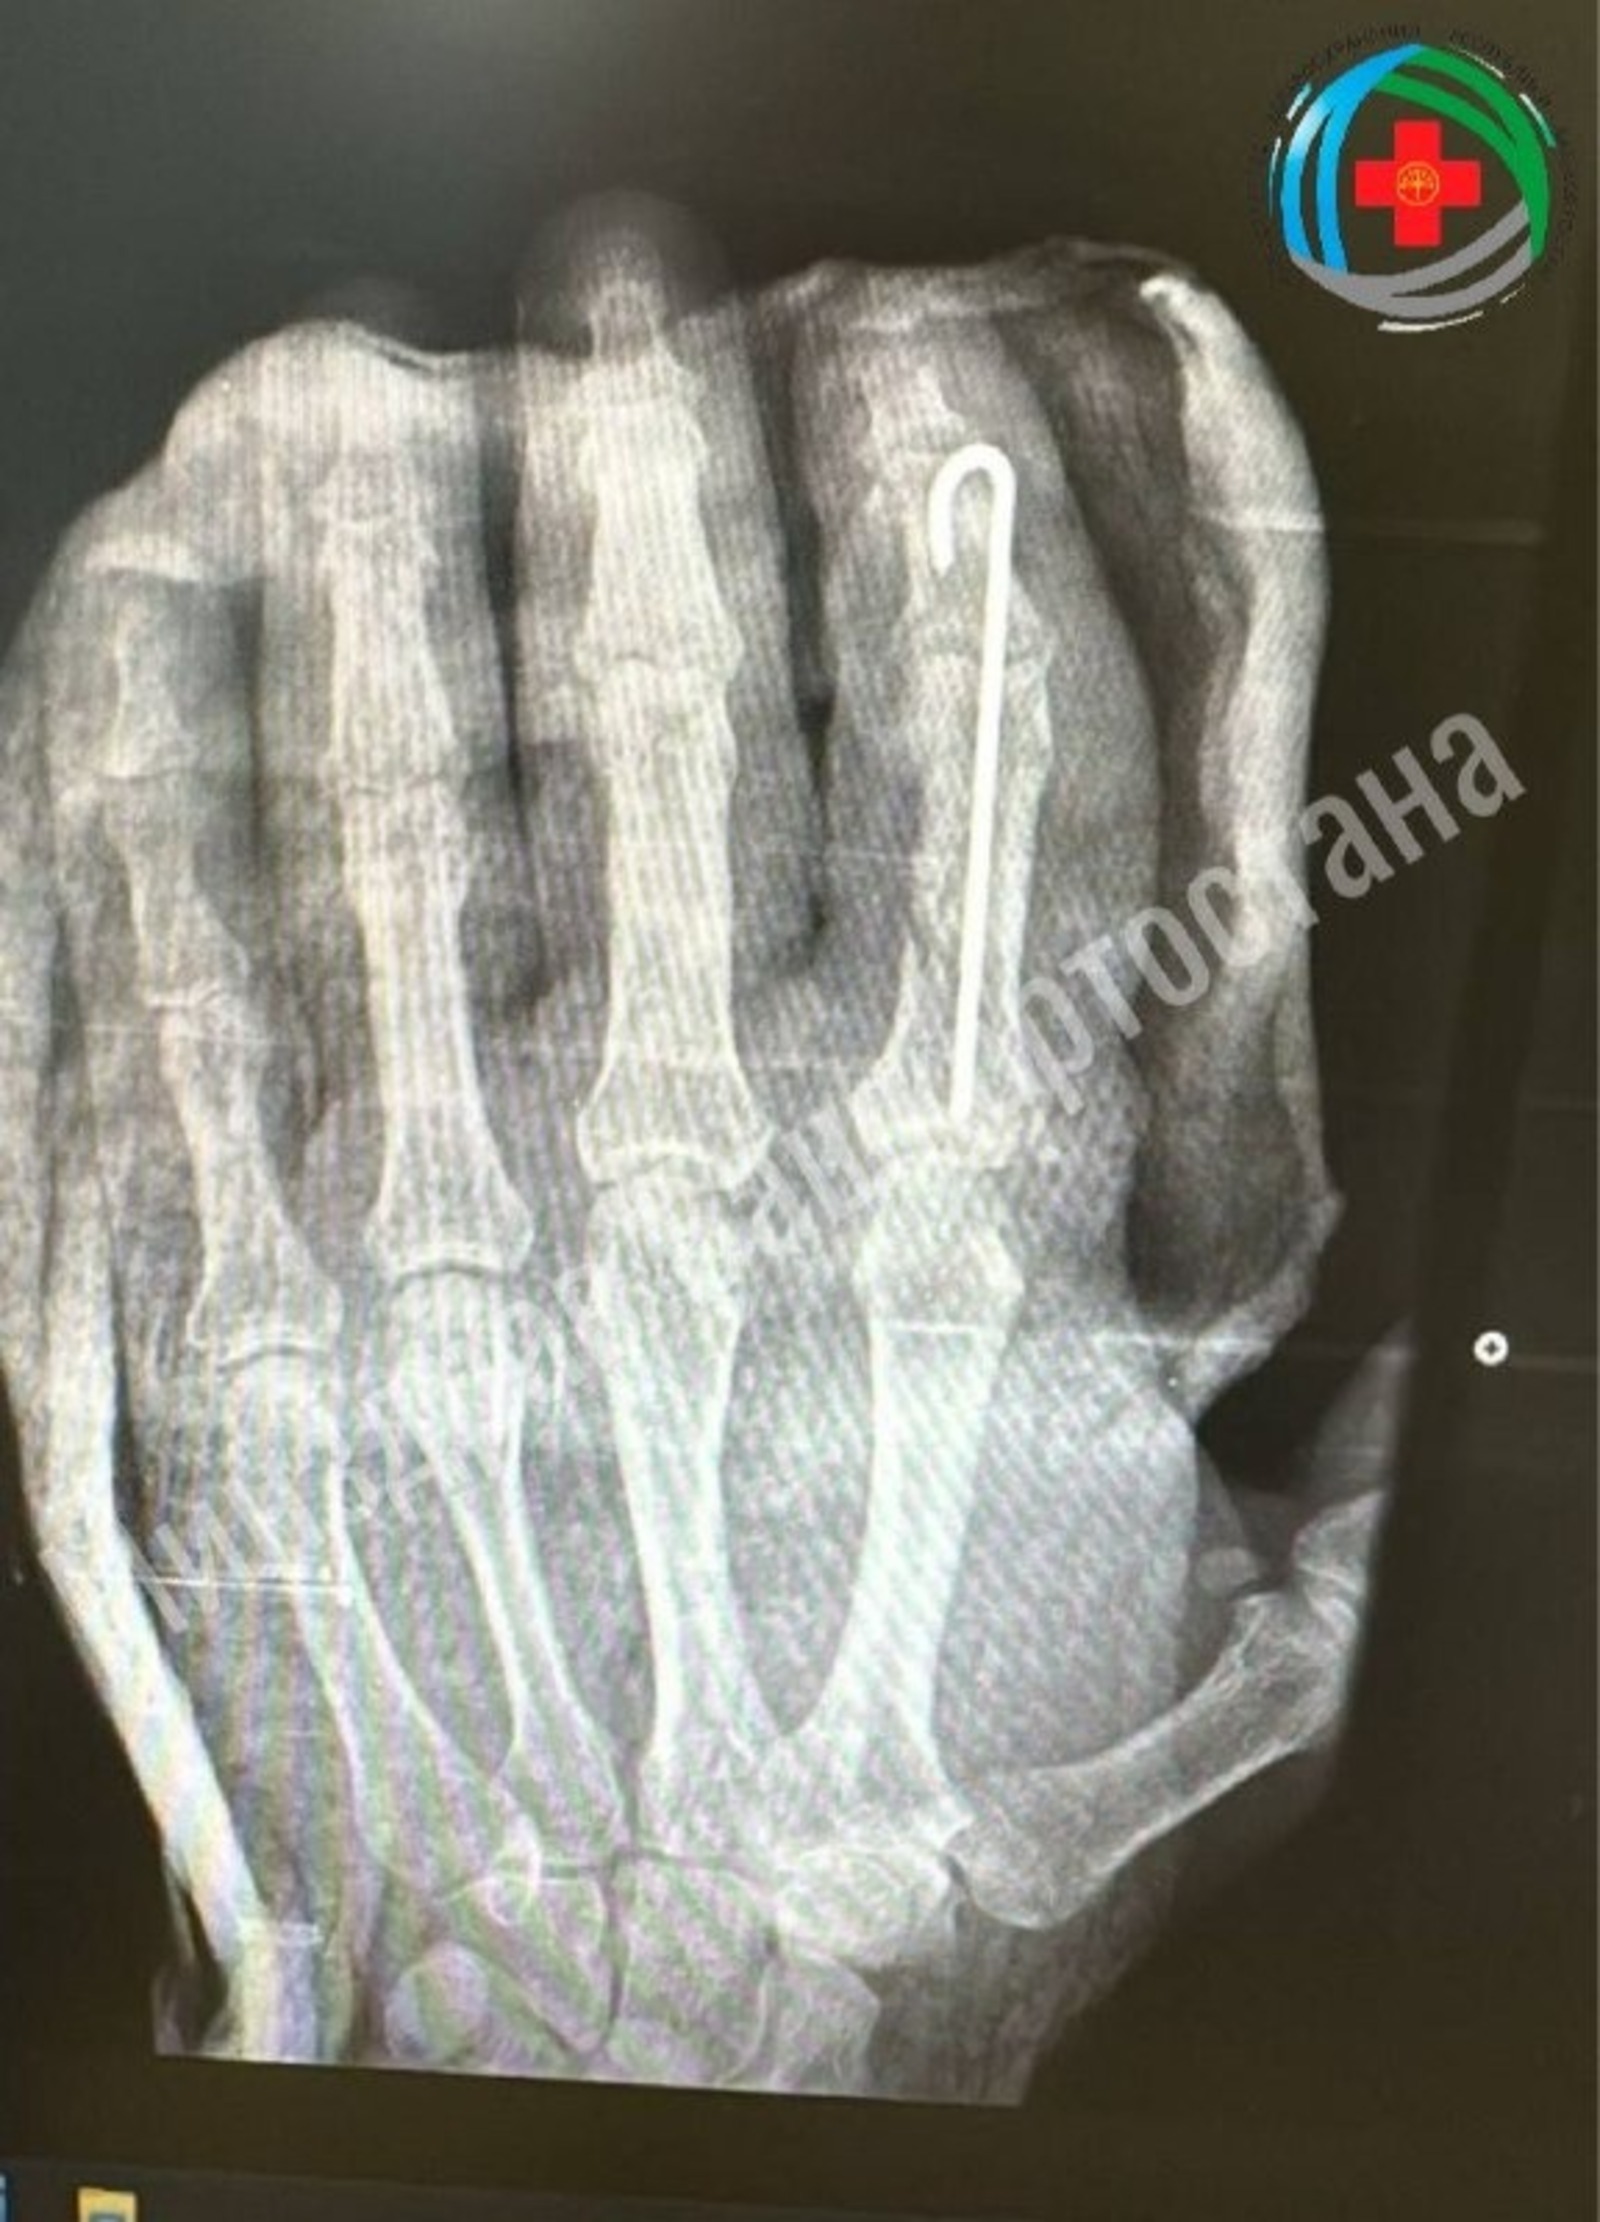

Они восстановили сосуды, зафиксировали кости и реконструировали мягкие ткани. Это позволило сохранить подвижность пальца.

Операция прошла успешно, мужчина уже может шевелить пальцем. Сейчас он проходит лечение: принимает лекарства, занимается физиотерапией и лечебной физкультурой. Врачи ожидают полного восстановления функций пальца.